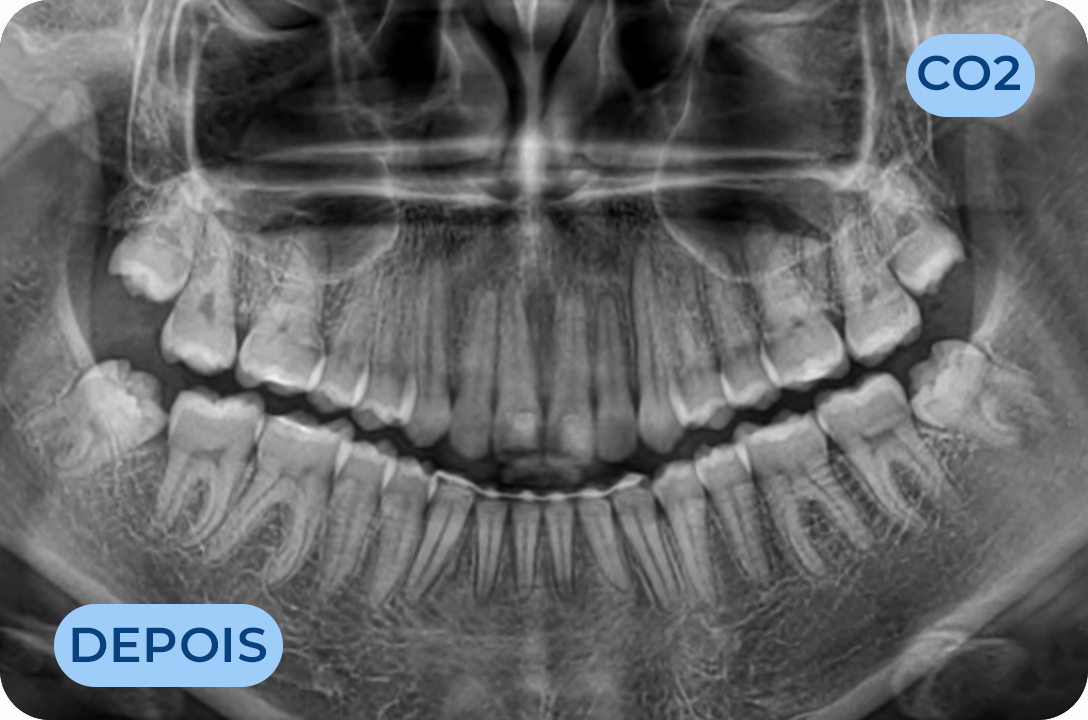

Ortodontia

É a especialidade da Medicina Dentária que se debruça sobre o estudo e correção das más posições dentárias e dos maxilares. Atualmente é possível tratar pacientes de todas as idades, no entanto a 1ª consulta deve ser realizada ainda na infância para intercetar eventuais problemas de desenvolvimento esquelético e funcional.

Odontopediatria

Especialidade da Medicina Dentária dedicada à manutenção da saúde oral dos bebés, crianças e adolescentes. Uma dentição definitiva saudável começa na infância com a prevenção e cultivo de hábitos saudáveis. Temos profissionais com formação específica na área, preparados com a tecnologia adequada para facilitar a consulta. Como a saúde do bebé começa antes do nascimento, todas as mães devem ser aconselhadas em relação aos cuidados antes e após o parto, na consulta de odontologia pré-natal que temos disponível na nossa clinica.